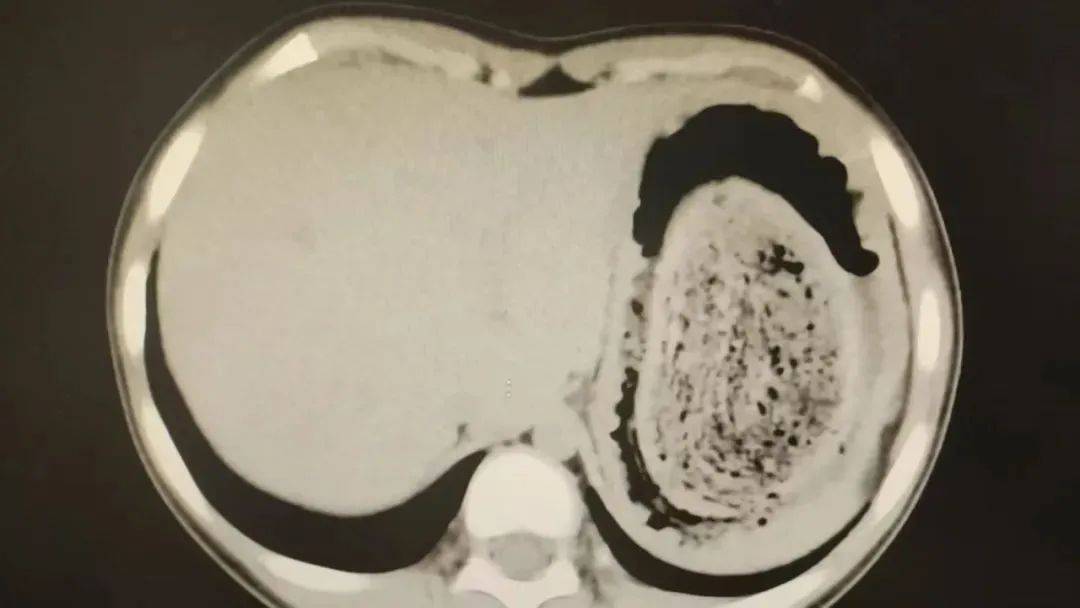

结果出来时,医生都惊呆了:小可的胃里,塞满了成团的头发,几乎占了胃容量的四分之三皇冠信用網在线注册。大量不能消化的物质,在胃酸的作用下发生变性,并与食物及其他物质结合形成团块,慢慢变成坚硬的“胃石”。

为了避免用手术方式去除头发团, 陈攸涛先让小可喝可乐软化“胃石”,再通过胃镜辅助取出头发,整个过程花了十几个小时,清理出的头发装了 两大盆皇冠信用網在线注册。

2024年10月,11岁女孩欢欢(化名)因腹痛难耐紧急送到医院,而就在两个月前,欢欢的父母发现她在拔自己的头发,偷偷吃掉皇冠信用網在线注册。经检查,医生发现她胃腔和肠管里有大块的毛絮状结石,几乎占据整个胃部。最终,一块长38厘米、宽15厘米、厚10厘米的毛发结石被取出。